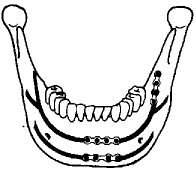

图1 Champy等提出的下颌骨骨折小型钛板固定复位的理想位置图(小型钛板应位于图中黑线上)

(3)钛板位置:根据Champy等对下颌骨应力曲线模似分析结果所提出的理想位置而定(图1),即两颏孔间的骨折线上应平行固定两个小型钛板; 而颏孔后方及下颌角区域的骨折线沿张力曲线固定1个钛板。